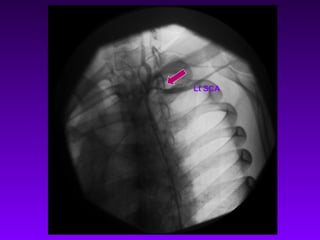

Lt SCA

Rt SCA

CC A

Abd Aorta

Rt CCA Long

Stenosis

Lt SCA Not Seen

Rt SCA Narrowing